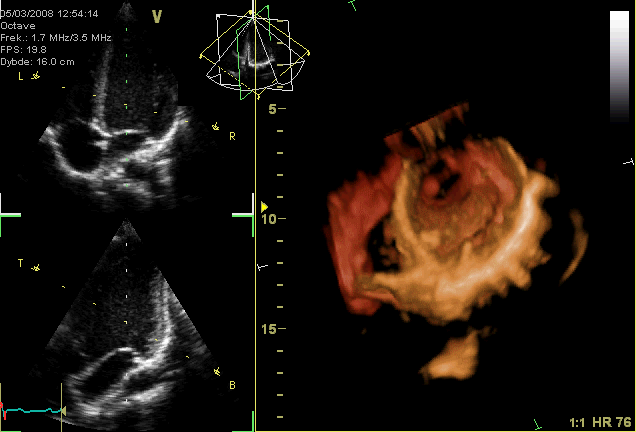

ملف:Apikal4D.gif

Apikal4D.gif (636 × 432 بكسل حجم الملف: 705 كيلوبايت، نوع MIME: image/gif، ملفوف، 15 إطارا، 0٫6ث)